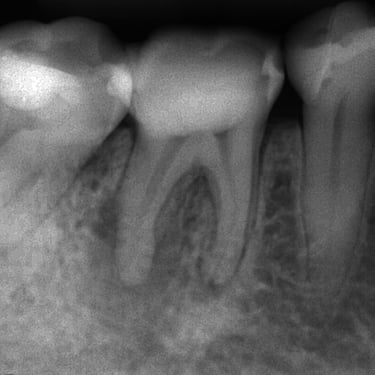

Calcificación Pulpar

La calcificación pulpar es la formación de depósitos de calcio dentro de la pulpa dental, que puede dificultar el tratamiento de conducto.

Los pacientes generalmente no tienen síntomas, pero pueden experimentar sensibilidad.

El tratamiento incluye la eliminación de los depósitos durante el tratamiento de conducto. Es importante tratarlo para evitar complicaciones durante el procedimiento.